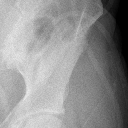

胫腓骨上段粉碎性骨折1(14.68MB)

胫腓骨上段粉碎性骨折2(10.09MB)

胫腓骨上段粉碎性骨折1

胫腓骨上段粉碎性骨折2